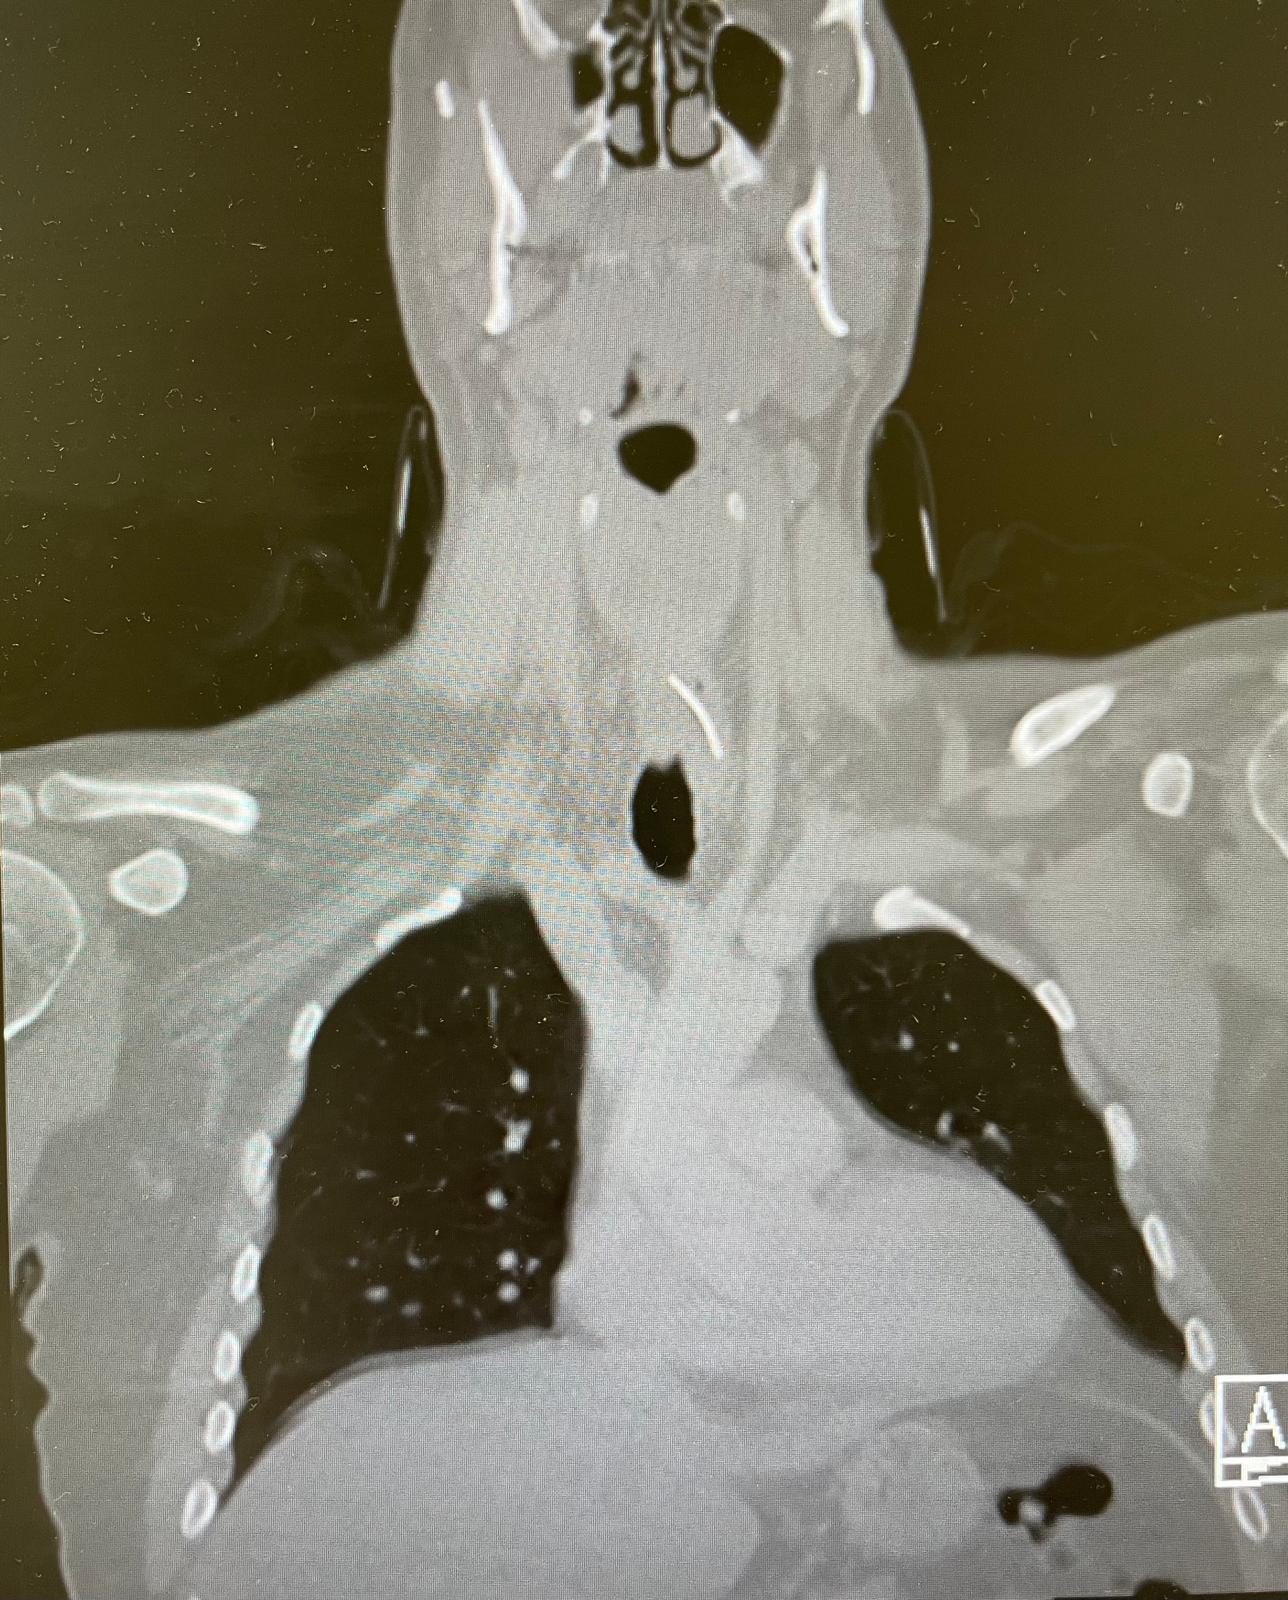

תושב ירושלים שאכל כריך טונה חשב שבלע עצם דג, אך בבדיקת CT התברר כי בוושט שלו נעוץ חוט ברזל חד באורך 3 ס"מ. הוא הובהל לניתוח חירום במרכז הרפואי שערי צדק

ד"ר אור שטריקמן, מתמחה בכירה במחלקת אף אוזן גרון, סיפרה כי בשל הרקע של אכילת דג עלה תחילה חשד לעצם תקועה. עם זאת, עוצמת הכאב ומשך הזמן החריג הובילו לביצוע בדיקת CT, שהציגה גוף זר בוושט העליונה.

צילום באדיבות המרכז הרפואי שערי צדק

ד"ר אוהד כהן, רופא בכיר ואחראי תחום ניתוחי מיתרי קול וגרון במחלקה, ציין כי בניתוח אנדוסקופי דחוף דרך הפה נשלף חוט ברזל חד מאוד באורך 3 ס"מ, שכבר גרם לפצע בדופן הוושט. לדבריו, כל איחור נוסף עלול היה להוביל לזיהום קשה ולסיבוכים.